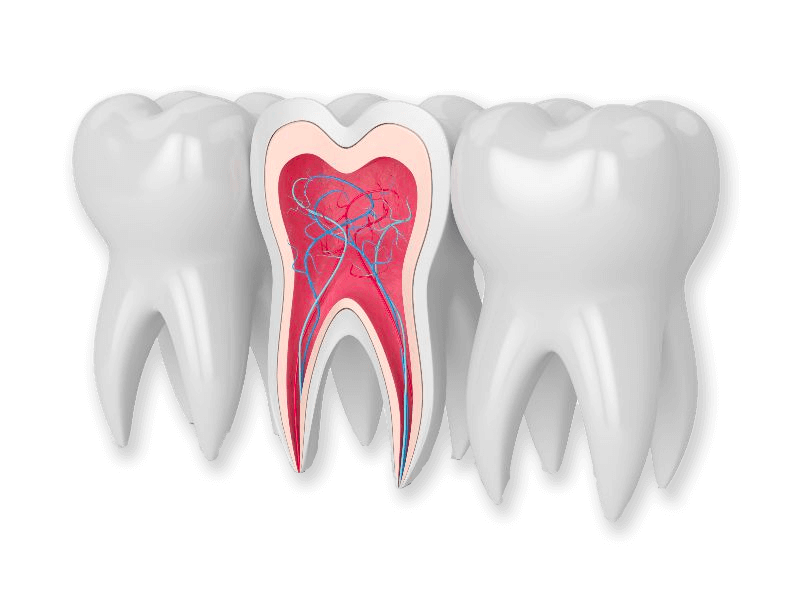

- حفظ دندان : در صورتی که دندان شما دچار عفونت ریشه باشد، درمان ریشه میتواند دندان را از از دست دادن نجات دهد. این فرآیند با تخلیص از عفونت و پر کردن فضای خالی داخل دندان انجام میشود.

- از بین بردن بافت مرده : پس از تشخیص، در مرحله بعدی بافت مرده و بافت آسیب دیده از دندان باید از بین برود تا به عفونت پایان داده شود.

- پر کردن فضای خالی : پس از تمیز کردن داخل دندان، فضای خالی با مواد ترمیمی پر میشود. این مواد معمولاً از نوع رزینهای کامپوزیت یا آمالگام است.